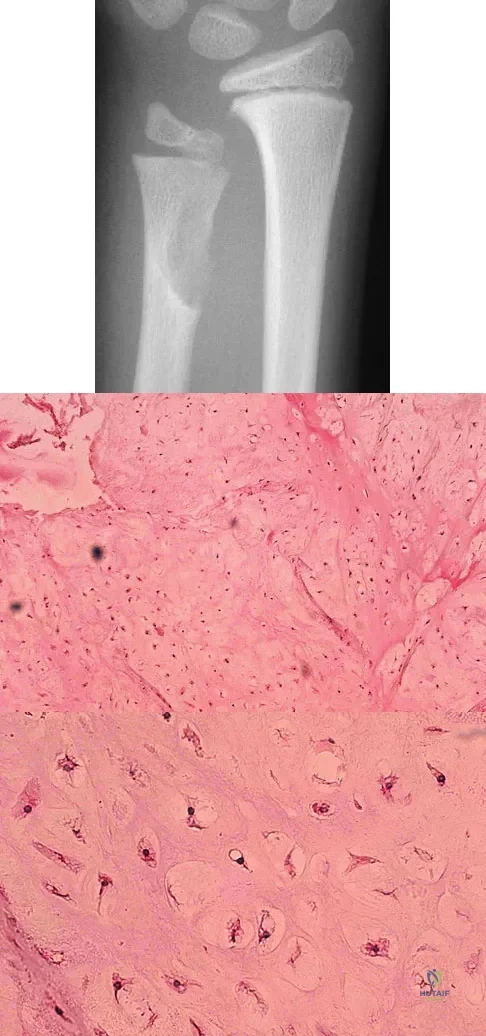

A 10-year-old boy has had wrist pain for the past 3 months. He denies any history of trauma. He reports mild tenderness associated with a palpable mass. A radiograph and biopsy specimens are shown in Figures 52a through 52c. What is the most likely diagnosis?